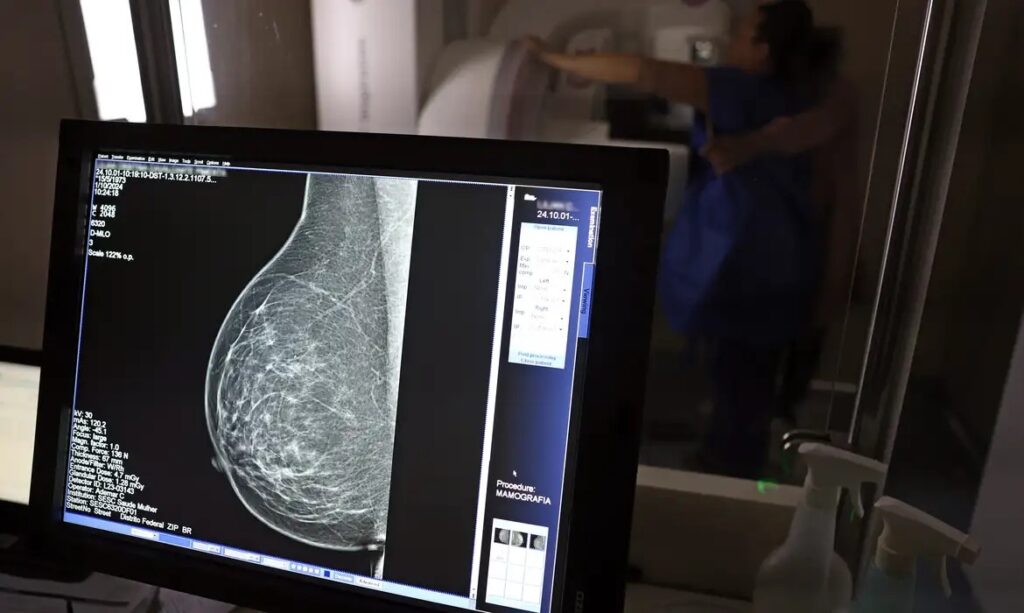

Ministério da Saúde passa a recomendar mamografia a partir dos 40 anos

O Ministério da Saúde passou a recomendar o acesso a mamografia, via Sistema Único de Saúde (SUS), para mulheres de 40 a 49 anos – mesmo que não haja sinais ou sintomas de câncer de mama. De acordo com a pasta, a faixa etária concentra 23% dos casos da doença, e a detecção precoce aumenta as chances […]